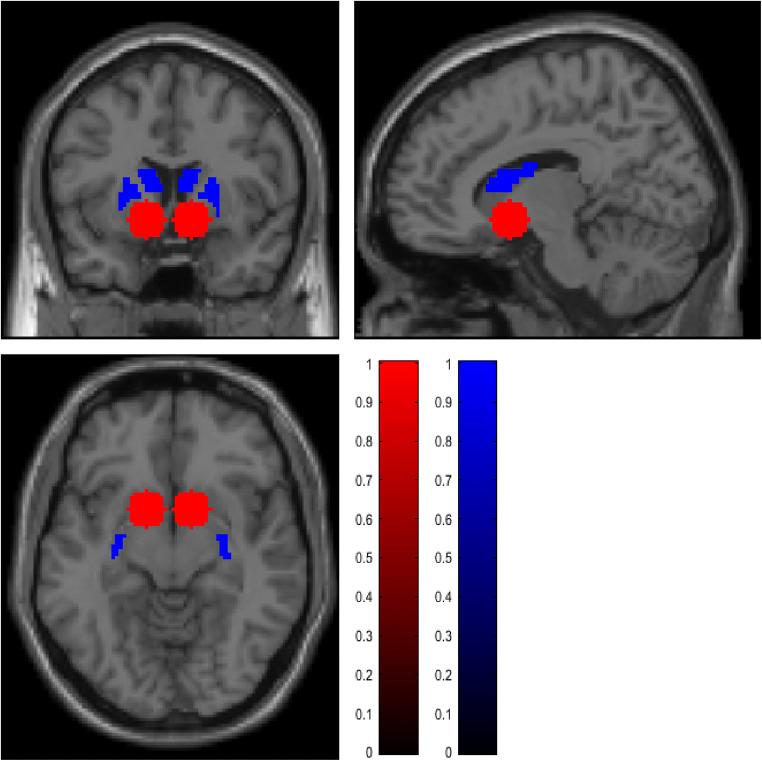

We tested the effect of a single dose of 18 mg nalmefene on neuronal cue-reactivity in the ventral and dorsal striatum and subjective craving.

An a priori defined region of interest (ROI) analysis of fMRI data from 15 participants revealed that nalmefene reduced alcohol cue-reactivity in the ventral, but not the dorsal striatum. Additionally, the subjective craving was significantly reduced after the cue-reactivity task under nalmefene compared to placebo.

我们测试了单次 18 毫克纳美芬对腹侧和背侧纹状体神经元线索反应性以及主观渴求的影响。

15 名参与者的 fMRI 数据的预先定义的感兴趣区域(ROI)分析显示,纳美芬降低了腹侧纹状体而非背侧纹状体的酒精线索反应性。此外,与安慰剂相比,在纳美芬下进行线索反应性任务后,主观渴求明显降低。